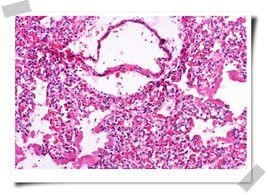

肺透明膜形成過程

肺葉氣腫圖像雖有先天性肺發育障礙的因素,但也有後天支氣管被壓迫的病例,故此病也被稱為“新生兒” 肺葉氣腫或“嬰幼兒”肺葉氣腫,而不宜稱為“先天性”肺葉氣腫。其特徵是:一葉或一段肺組織過度膨脹,壓迫正常肺組織、縱隔器官及心血管系統,是造成嬰幼兒急性呼吸窘迫的常見病因之一。僅見於新生兒或幼兒,1/3病例出生後即刻發病50%發生在出生後1個月,僅5%在出生後6個月發病,男多於女,常見於雙肺上葉(以左上肺葉最多見),其次為右肺中葉,下葉少見。臨床表現為單葉或單側肺透明膜病。理論上肺實質自身異常是此病的可能病因,但未被證實,有人研究切除後肺葉的形態學,可見肺泡數量增加,超過正常50%,並且肺泡大小正常或增大,氣管及血管的數量和結構正常,提示:此病為肺囊泡巨大症或出生後肺泡異常增加。

異常血管1.先天性肺葉氣腫 過度膨脹的原因和發病機制有很多,這種病被看成是臨床病理綜合徵可能要比看成單一病變要好,原發的病變可能在葉支氣管內(導致部分梗阻和繼發膨脹)或在肺實質內,前者占約50%,發病因素被分為3類:①支氣管外壓迫:約占7%可有多種原因壓迫支氣管最常見為異常血管,如大的未閉動脈導管、異常走行的肺靜脈或迷走肺動脈(左肺動脈源於右側)等,也可見於異常增大的淋巴結或支氣管旁腫物(支氣管源性囊腫)的壓迫使受壓支氣管遠端肺組織氣腫;②支氣管管壁異常:約2/3的病例明確或可疑有支氣管軟骨缺如或發育不良等,造成氣管塌陷、梗阻,而繼發肺葉遠端阻塞性氣腫;③支氣管腔內梗阻:可為先天性或獲得性前者包括黏膜皺襞或局限性支氣管狹窄後者包括黏液栓或肉芽組織。文獻報導:切除的標本中25%~40%可見支氣管軟骨缺陷或變形,仍有50%以上的病例原因不明。40%~50%的嬰幼兒患者合併其他畸形,如:先天性心臟病、齶裂等。